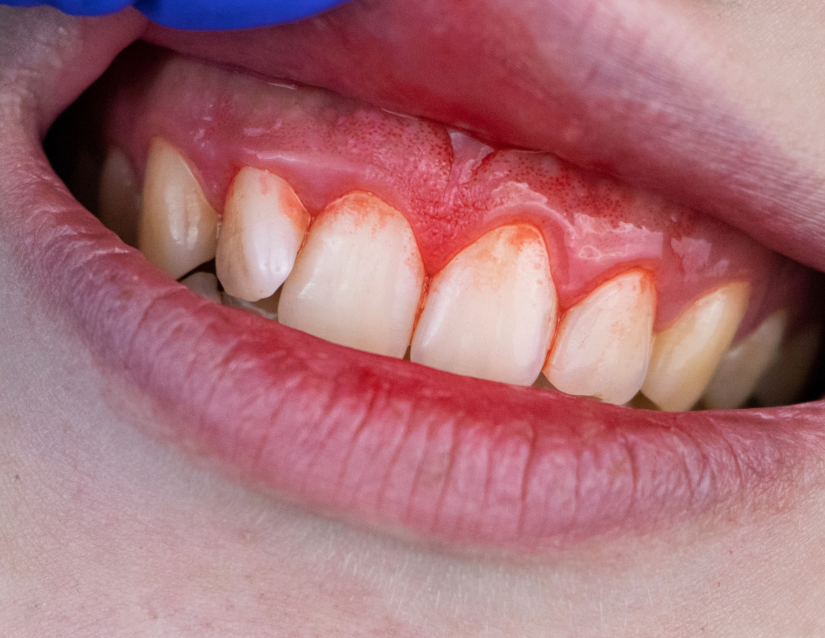

Periodontitis

Ahora, la placa bacteriana y el sarro pueden dañar también otros tejidos, a las bolsas periodontales y afectar a la raíz del diente.